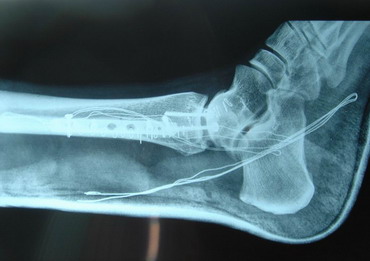

14 - 5 - 07 El torero se interviene hoy a la 12,30 horas en la Clínica Sagrado Corazón de Sevilla. Se confirma diagnóstico provisional hecho en la enfermería de la plaza de Osuna. Fractura de tibia y peroné. Con las siguientes connotaciones: La fractura de peroné es completa y compleja consta de 4 fragmentos diferentes con desplazamiento de los mismos. es decir una fractura conminuta. La tibia presenta fractura maleolar con desplazamiento y además con respecto al tobillo existe una subluxación de la articulación debida a la rotura o explosión de la cápsula articular con desflecamiento de la misma. En resumen un cuadro complejo de tobillo inestable que precisa intervención quirúrgica inmediata. Se estabilizan las fracturas, se sutura la cápsula anterior, se reduce la subuxación, se administran factores de crecimiento y se inmoviliza extremidad. Pronóstico grave. Se estima un tiempo de recuperación de 90 días. Dr. Minguet. Dr. Periañez. Dr. Vaz. Dr. Morales |